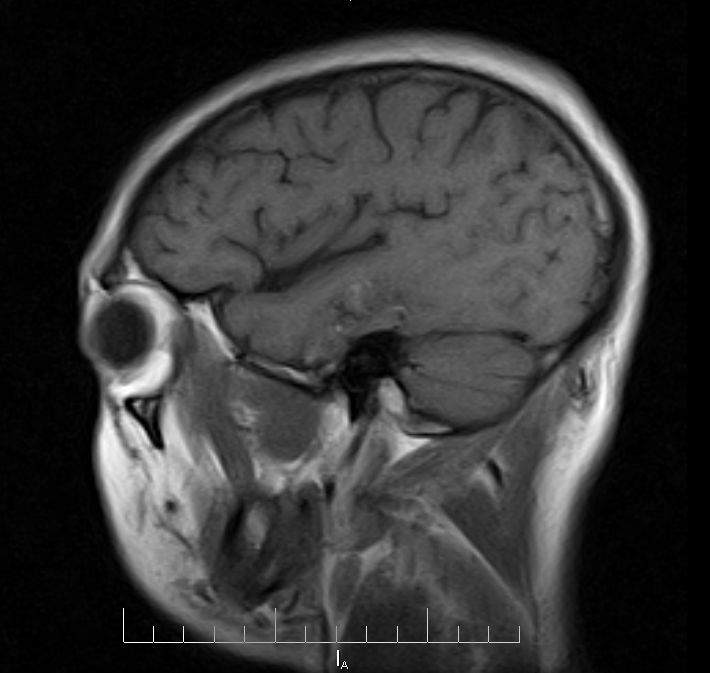

标题: MRI2379:30岁,男,癫痫10年,请各位看一下;CT示:左颞叶钙 [打印本页]

标题: MRI2379:30岁,男,癫痫10年,请各位看一下;CT示:左颞叶钙

左颞叶区见不规则点状混杂信号影

支持2楼 左颞叶区见不规则点状混杂信号影,考虑动静脉畸形。

考虑左侧颞叶脑血管畸形(avm)。----t1低等高混杂信号,t2等高信号周边较多流空血管影[冠状位明显],mra左侧大脑中动脉受压,远侧聚集.